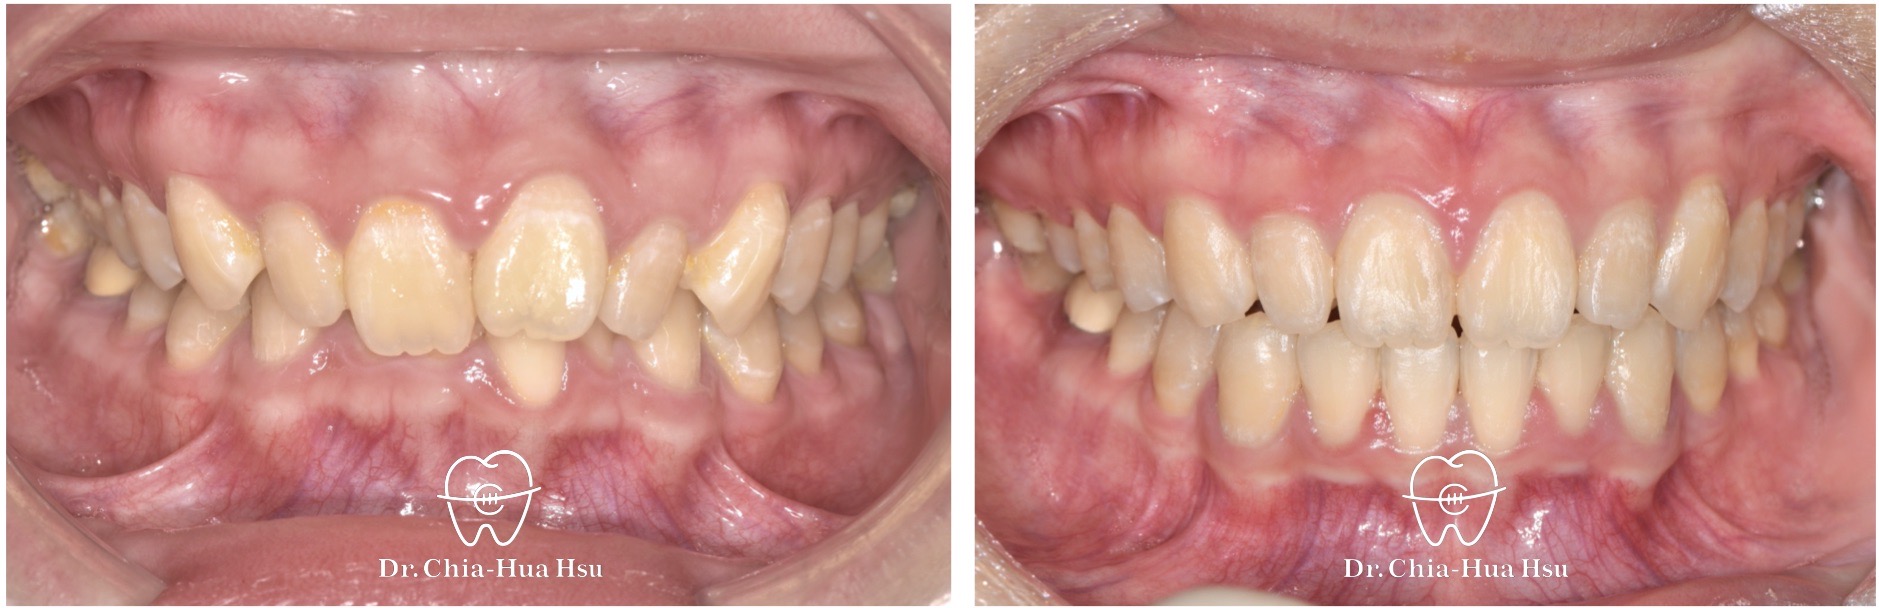

- 問題分析:患者是標準的骨骼一類咬合(Skeletal Class I)伴隨齒列擁擠以及深咬。

- 治療方式:使用傳統金屬矯正器,搭配二級橡皮筋牽引(Class II elastics)。

- 治療時間:1 年 3 個月。

- 治療結果:齒列排齊,深咬有顯著改善,笑容更有自信。

治療前

治療後